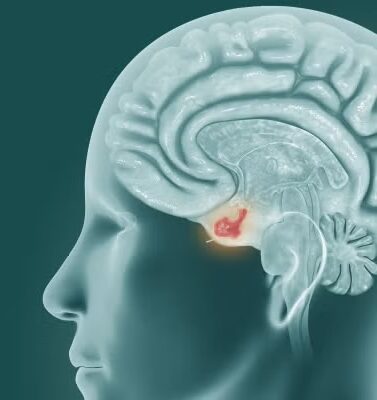

Los adenomas hipofisarios son las neoplasias más comúnmente encontradas en la región selar, ocupando la hipófisis. Estos tumores, en su mayoría benignos, pueden manifestarse con síntomas relacionados con el efecto de masa, como cefalea o pérdida de la visión, debido a la presión ejercida sobre estructuras circundantes.

Además de los adenomas, existen otros tipos de tumores que pueden afectar la hipófisis, incluyendo lesiones benignas como quistes de la bolsa de Rathke, craneofaringiomas, pituicitomas, meningiomas, así como tumores malignos como los de células germinales, cordomas, linfoma primario y metástasis. Además, se encuentran lesiones no neoplásicas como la hipofisitis y la sarcoidosis.

Los síntomas causados por estos tumores pueden variar según su tipo y ubicación. Tumores selares y supraselares pueden generar síntomas relacionados con el efecto de masa, como cefalea debido a la presión intracraneal o pérdida de visión, que puede estar asociada a la compresión de las estructuras ópticas. En el caso de los tumores hipofisarios funcionales, la hipersecreción de hormonas puede dar lugar a síntomas específicos asociados a la función hormonal alterada. Por último, algunos tumores pueden causar síntomas relacionados con la insuficiencia hipofisaria, ya que pueden interferir con la producción normal de hormonas por parte de la glándula.